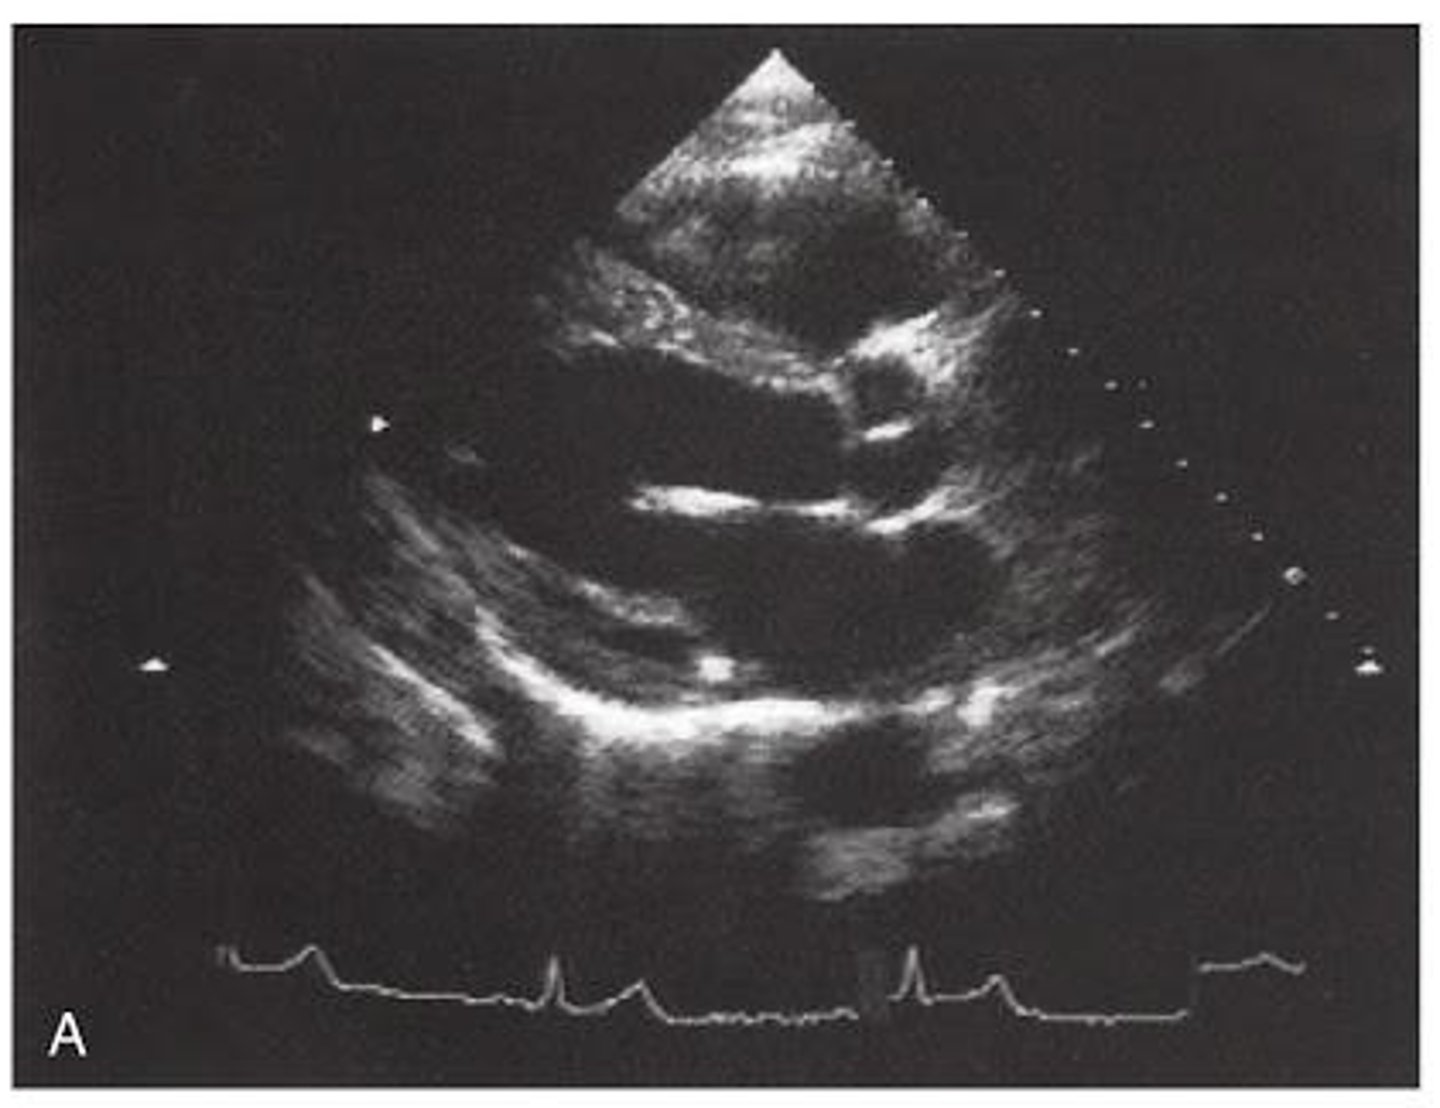

PSLA is used to visualize ____ and _____

MV and AoV